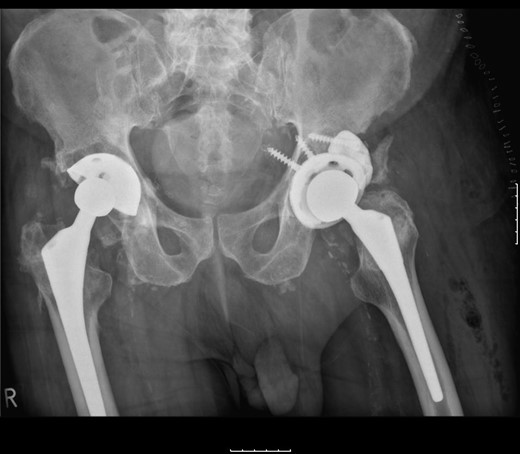

The patient was subsequently scheduled for revision surgery of the acetabular component. Intraoperatively, there was blackening of the periprosthetic tissue and metal debris throughout. The PE liner remained engaged within the acetabular cup with significant wear through its back. The femoral head had migrated superolaterally through the acetabular cup and was articulating with the superior acetabular wall causing bony destruction. The acetabular cup remained well fixed within the acetabulum with good bony ingrowth (Figs 2 and 3).

The acetabular component showing extreme wear-through and metallic fragments.